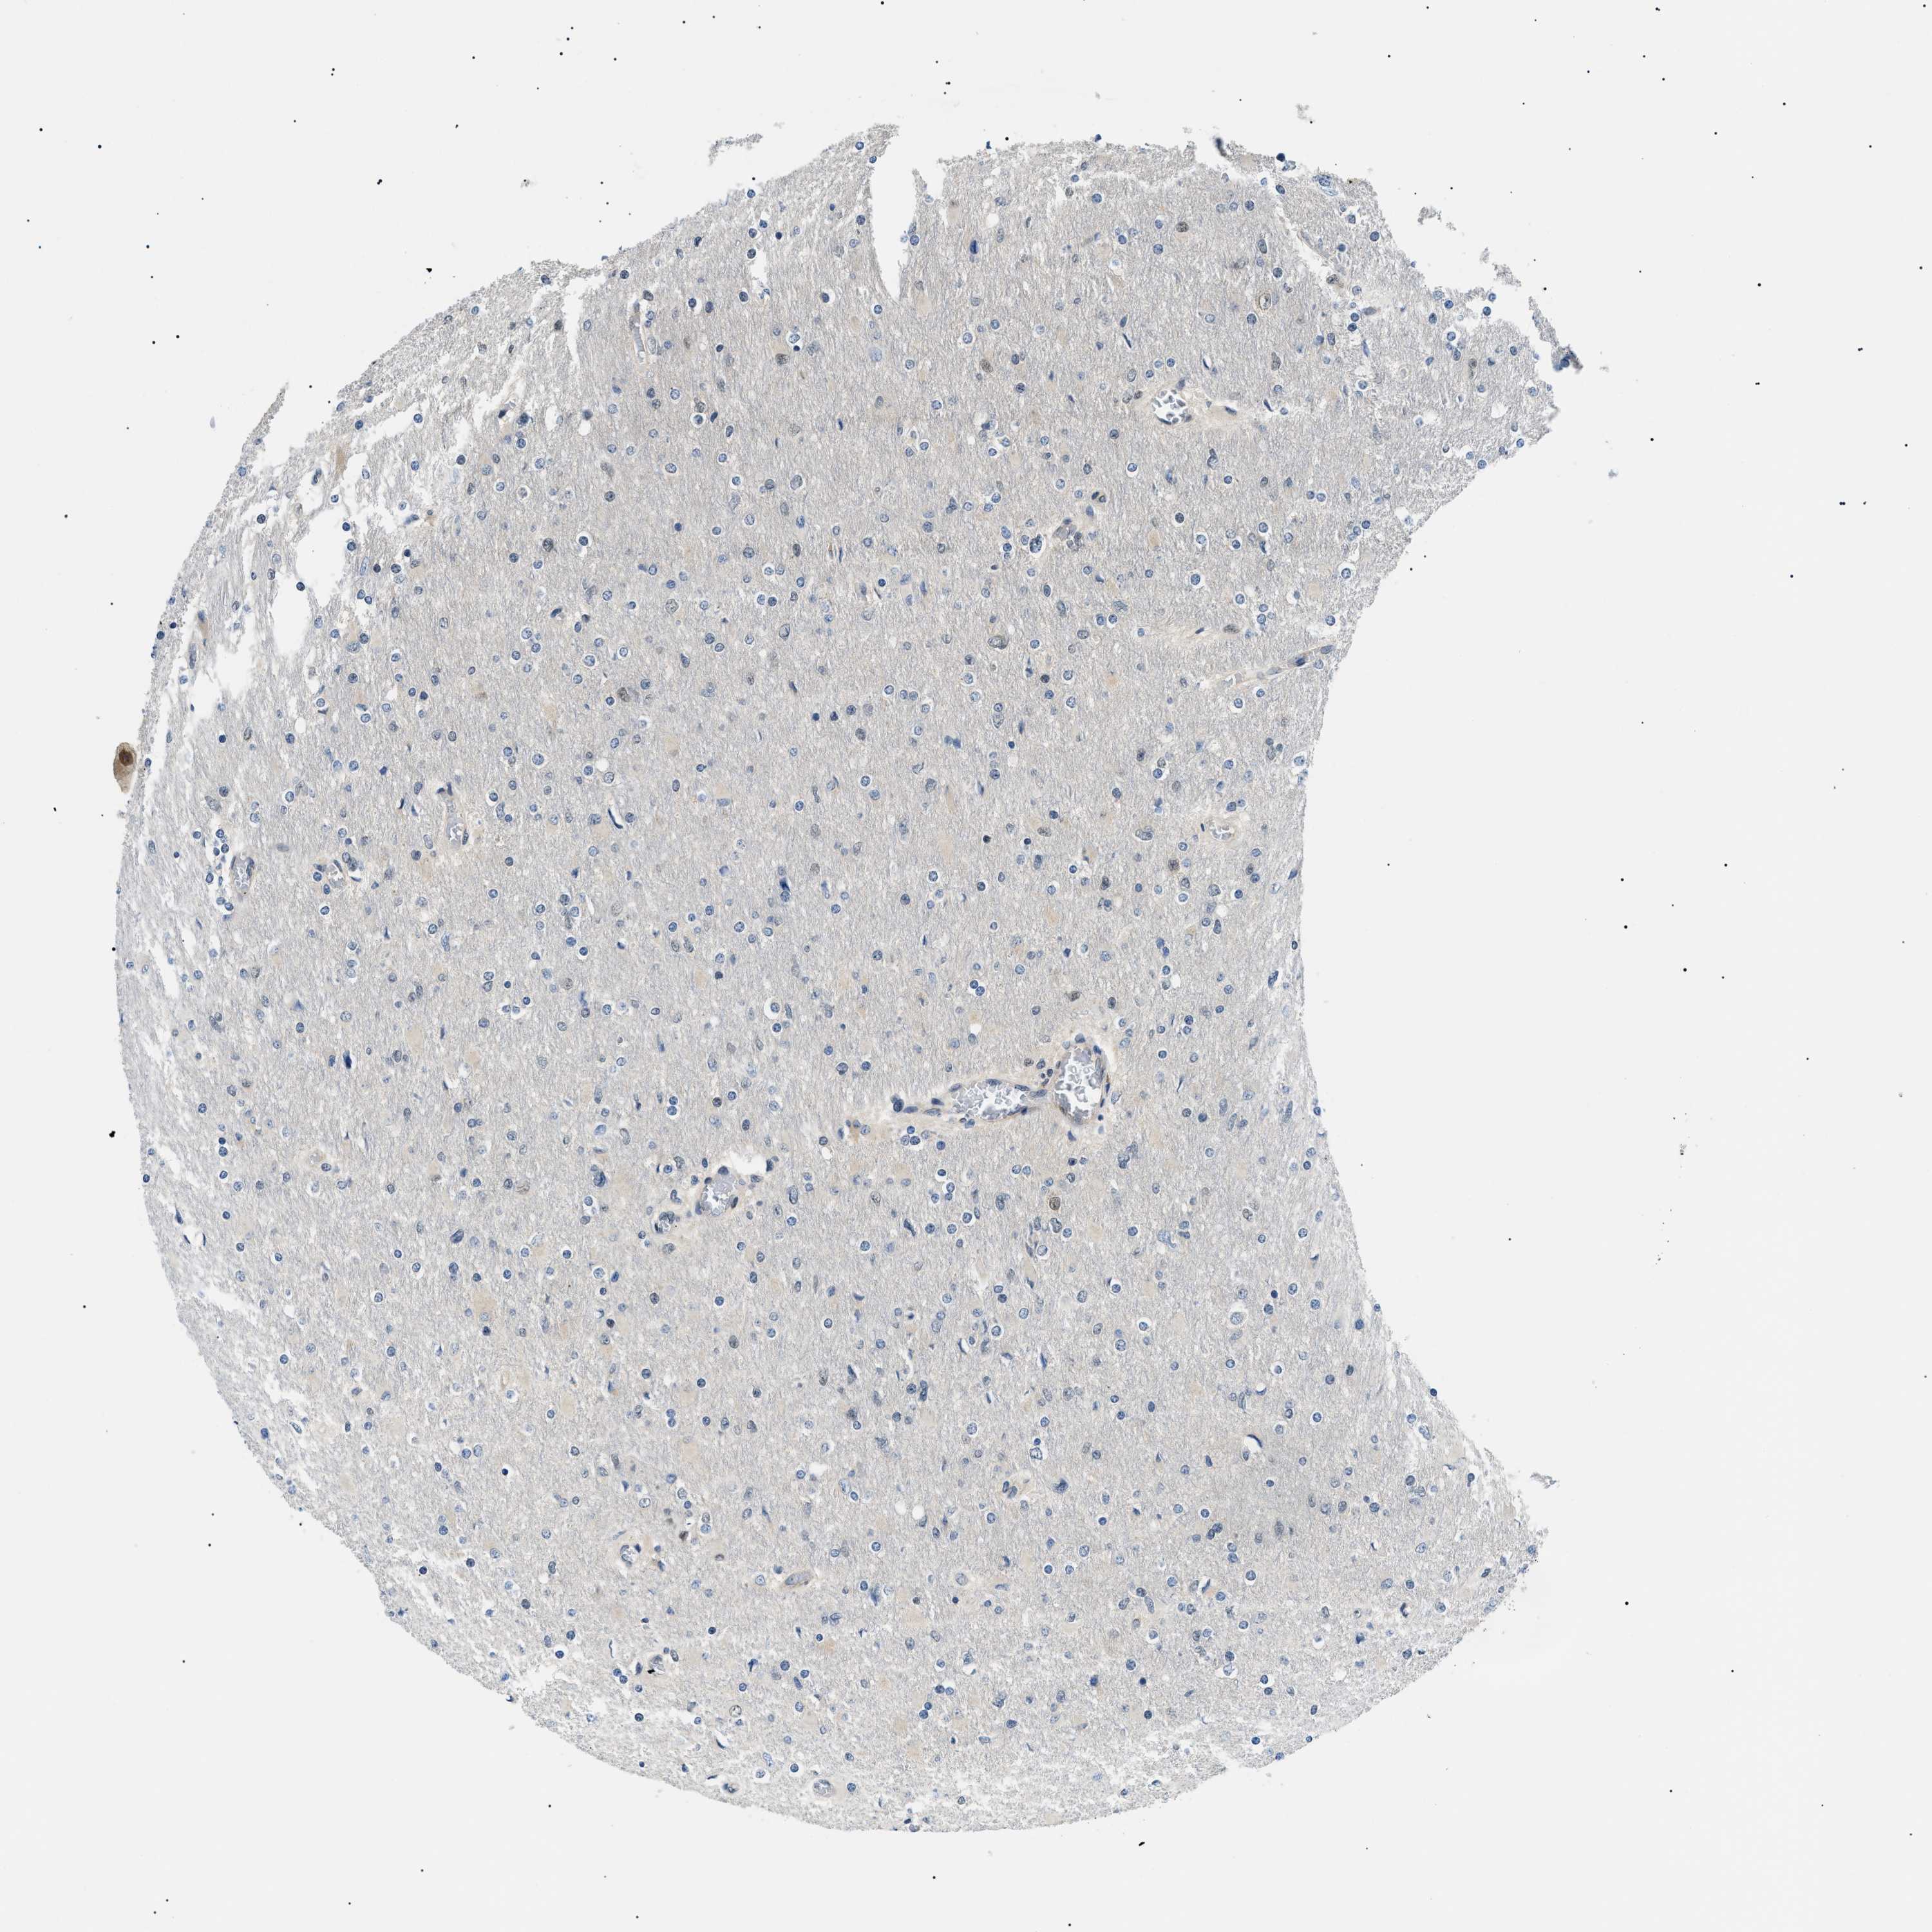

GLIOMA - Protein expressioni

A mouse-over function shows sample information and annotation data. Click on an image to view it in a full screen mode. Samples can be filtered based on level of antibody staining by selecting one or several of the following categories: high, medium, low and not detected. The assay and annotation is described here.

Note that samples used for immunohistochemistry by the Human Protein Atlas do not correspond to samples in the TCGA dataset.

Antibody stainingi

Antibody staining in the annotated cell types in the current human tissue is reported as not detected, low, medium, or high, based on conventional immunohistochemistry profiling in selected tissues. This score is based on the combination of the staining intensity and fraction of stained cells.

Each image is clickable and will lead to virtual microscopy that enables deeper exploration of all samples and also displays staining intensity scores, fraction scores and subcellular localization as well as patient and tissue information for each sample.

Antibody HPA019824

Antibody CAB015201

Staining

High

Medium

Low

Not detected

Intensity

Strong

Moderate

Weak

Negative

Quantity

>75%

75%-25%

<25%

None

Location

Nuclear

Cytoplasmic/membranous

Cytoplasmic/membranous,nuclear

Glioma, malignant, High grade

Glioma, malignant, Low grade